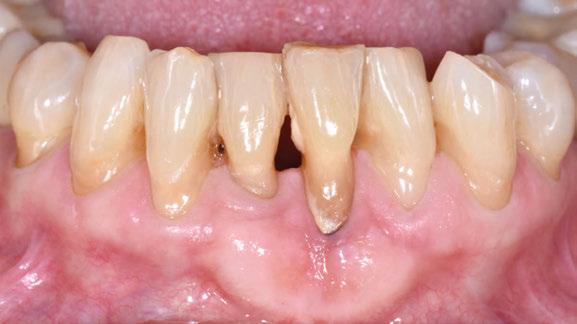

CASO CLÍNICO 2 (FIGURAS 8-15)

Paciente de 64 años de edad que acude a consulta refiriendo haber sido intervenida hace años para el tratamiento de sus recesiones gingivales. Refiere que, además, sus recesiones han progresado desde entonces.

A la exploración clínica se observan recesiones RT3 en el quinto sextante, siendo el diente en posición de 31 el que peor situación basal presenta. En este caso existe una banda de encía queratinizada

en apical que podemos pensar que se logró en la intervención previa realizada. A nivel de radiografía 3D se observa que adicionalmente presenta una dehiscencia ósea vestibular.

El diseño quirúrgico empleado es idéntico al del primer caso clínico. En este caso, adicionalmente, se desplaza la banda de encía queratinizada apical hacia coronal gracias al avance del colgajo.

Al combinarse la presencia de recesiones gingivales avanzadas con pérdida de inserción interproximal y dehiscencias óseas se utilizó nuevamente una lámina de cortical desmineralizada. La sutura realizada en este procedimiento quirúrgico es idéntica a la del primer caso clínico.

En un seguimiento a medio plazo, se puede observar un mantenimiento adecuado de los resultados en términos de salud periodontal, cobertura radicular, aumento de encía queratinizada y de profundidad de vestíbulo.